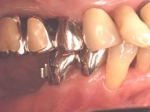

術前口腔内(正面観)

術後口腔内(正面観)もう入れ歯は要らなくなりました。